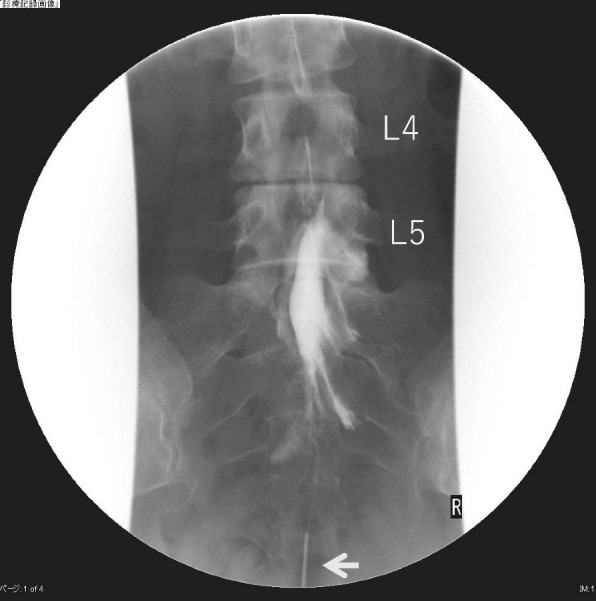

Case presentation: We encountered a patient with L5 lumbar epidural adhesions who reported pain even after receiving two epidural catheters. The catheters were placed in the L1/2 and L5/S intervertebral spaces. Analgesic effects were exerted when the L5/S catheter was withdrawn by 1 cm, suggesting that the catheter tip was initially placed inside the adhesion.